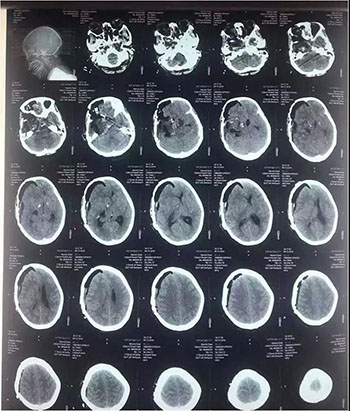

中脑海绵状血管瘤手术

术前

术后

颅眶沟通性肿瘤切除手术

术后(肿瘤全切)